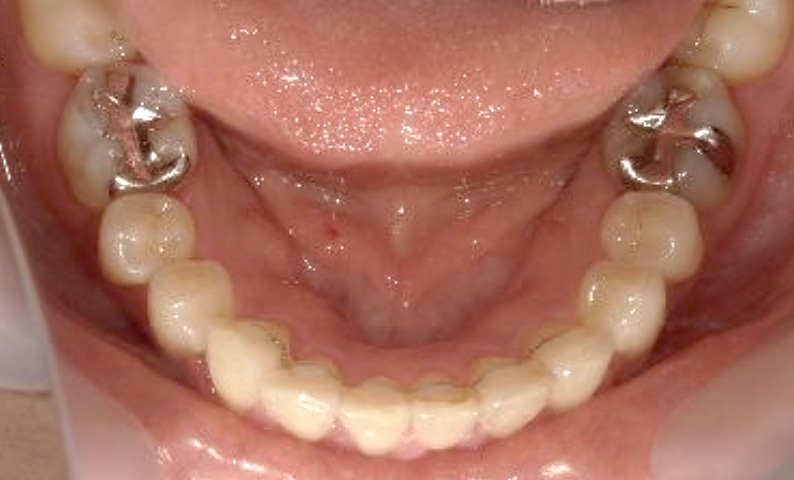

症例_023 上下顎の部分矯正

治療期間:11ヶ月金額:45万円+税女性前歯のガタガタ八重歯

| Before | After |

|---|---|

|